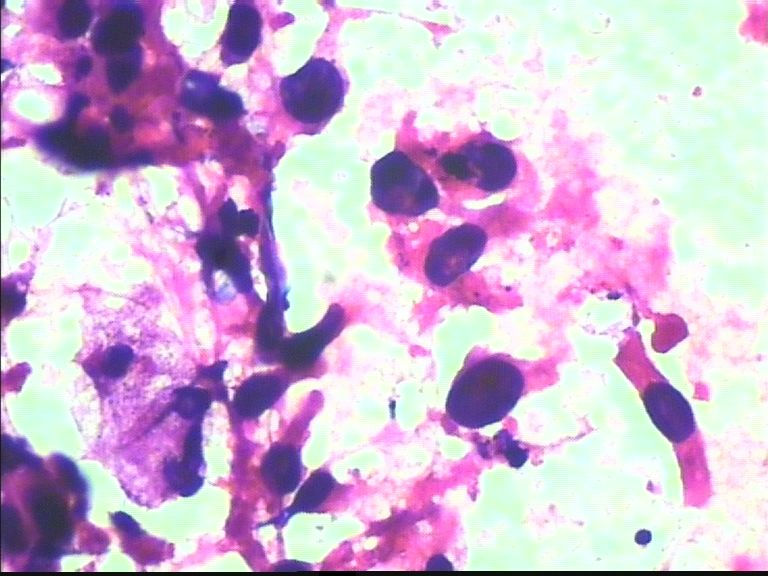

38岁 乳腺肿瘤 女

润性导管癌,细胞大小不一、异形明显、粘附性差,尤其是在同一堆细胞内。

非常明显的恶性肿瘤细胞,倾向浸润性导管癌。细胞异型性大,非常弥散,未见肌上皮细胞。

恶性肿瘤细胞

乳腺导管癌

导管癌